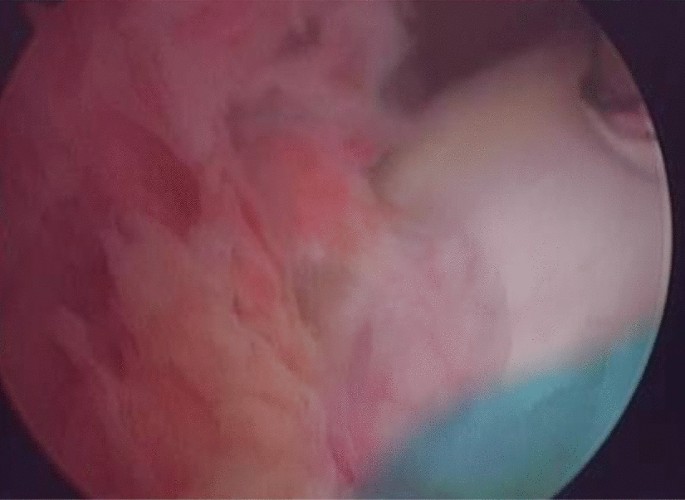

The surgical treatment methods were as follows: (1) the conventional arthroscopic approach was combined with additional posteromedial/posterolateral or superomedial/superolateral approaches; (2) synovial tissue culture during surgery and culture for at least 14 days, which represents the highest sensitivity index, was performed, and the results were compared with those of the puncture fluid; (3) necrotic and inactive tissues were widely and thoroughly removed, and fibrous tissue and clots were simultaneously removed; (4) the joint cavity was irrigated with an adequate amount of normal saline (10–15 L); (5) fibrin covering the surface of the ligament was gently removed; and (6) if a thickened inflammatory synovium was found during the operation (Fig. 3), it should be excised. However, this procedure may cause additional trauma to the knee joint and increase the risk of postoperative joint fibrosis.